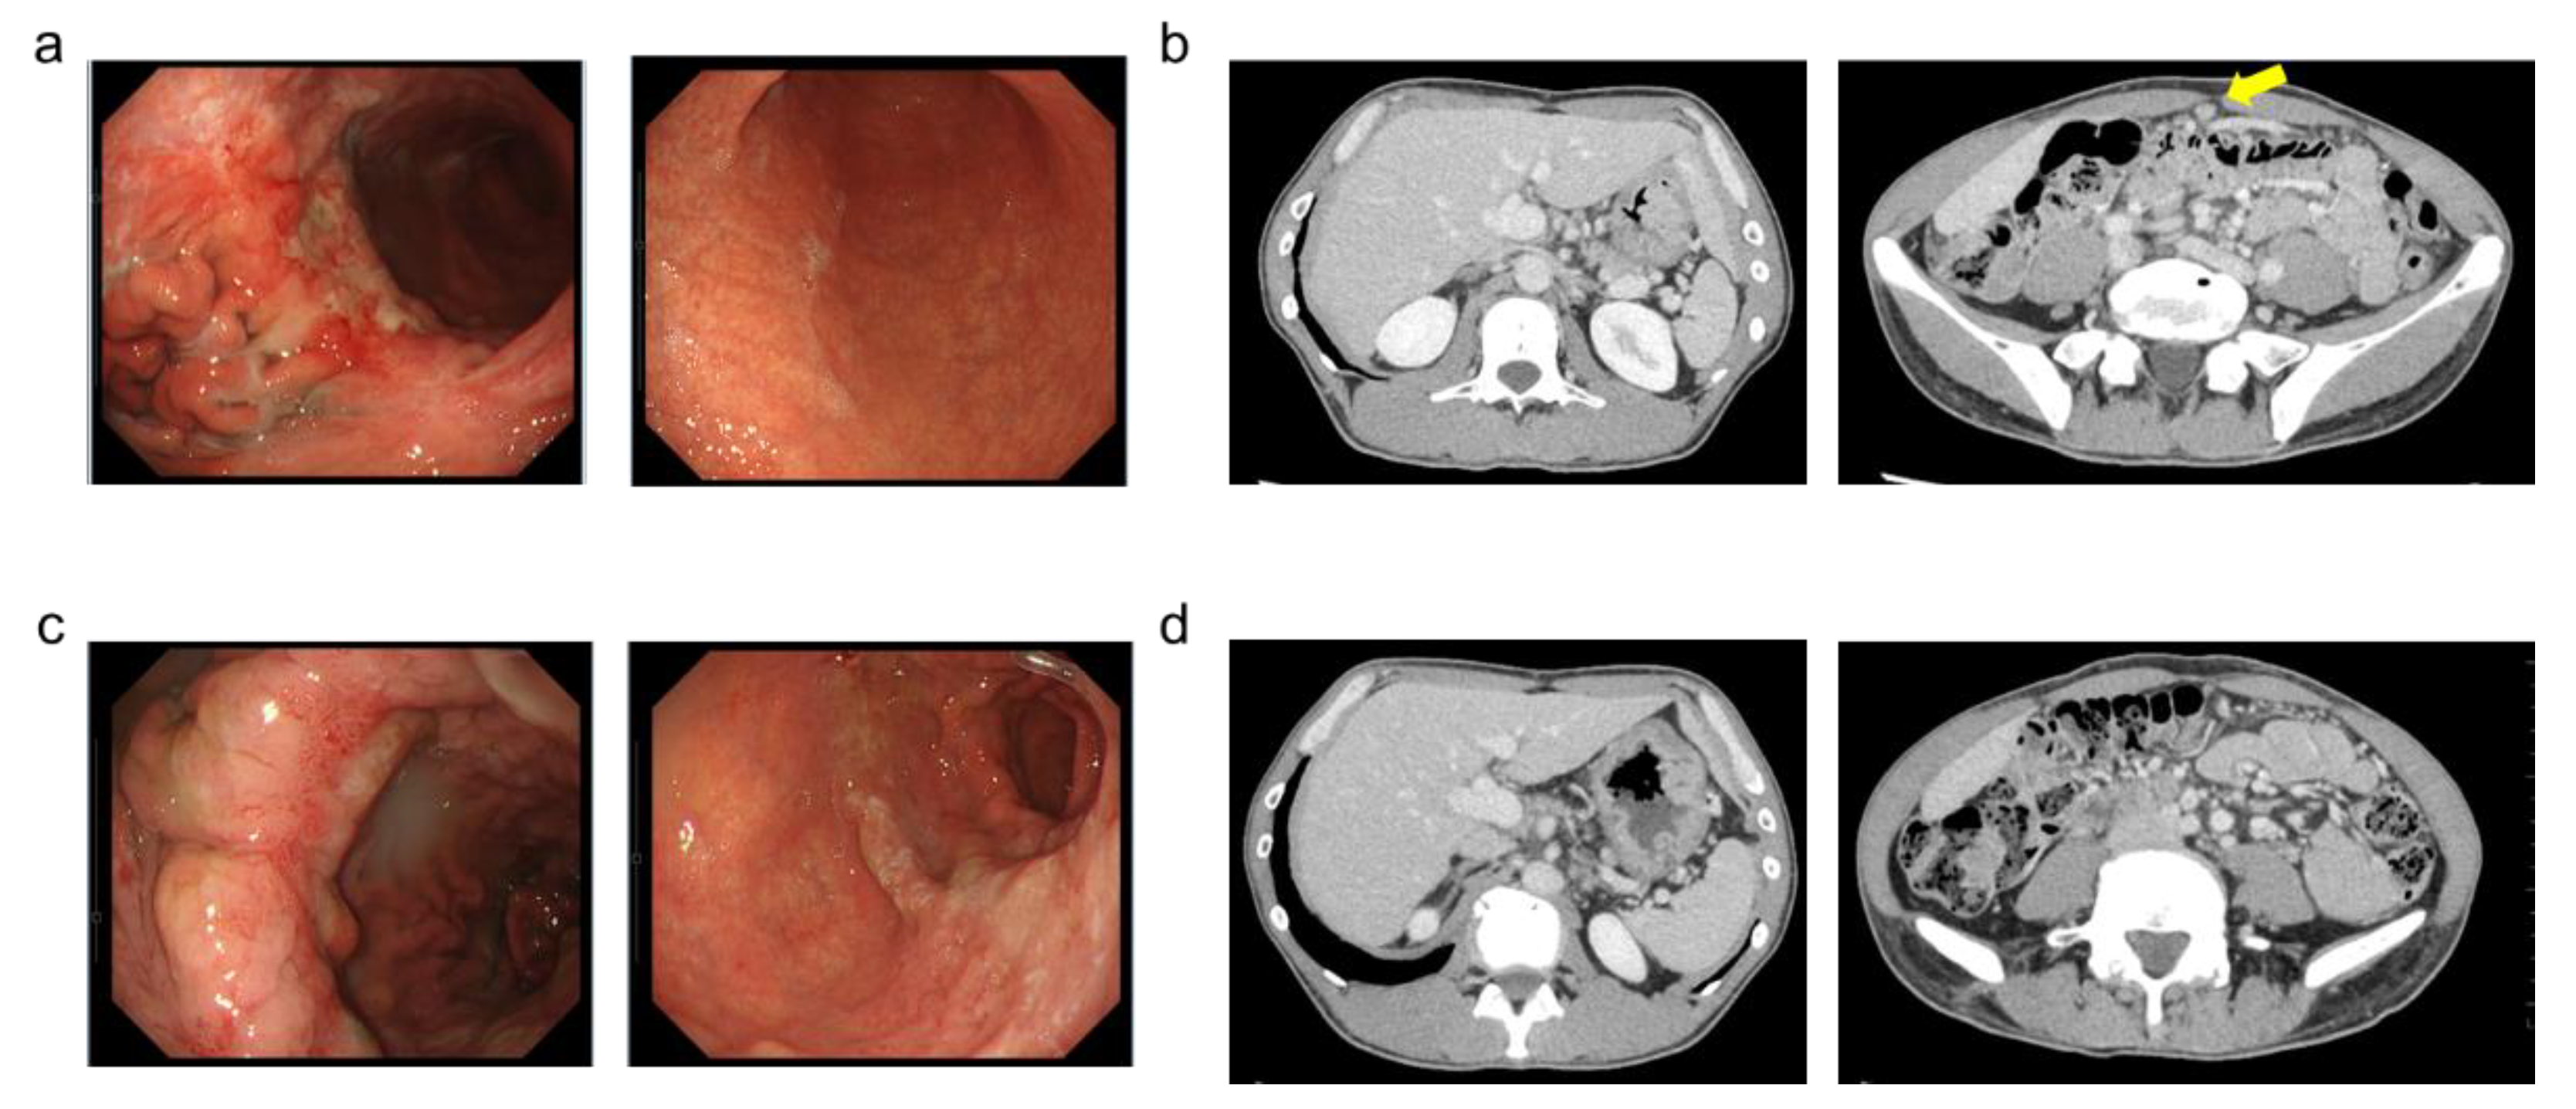

Laboratory data is shown in Table 1. Upper gastrointestinal endoscopy revealed a type 3 tumor in the middle portion of the greater curvature of the gastric body (Figure 1a). Biopsy confirmed poorly differentiated adenocarcinoma (Figure 2a). CT scan suggested peritoneal dissemination (Figure 1b), so after a multidisciplinary conference between internal medicine and surgery departments, systemic chemotherapy was recommended instead of surgery.

The main adverse events included nausea and grade 1 hypoalbuminemia according to the Common Terminology Criteria for Adverse Events (CTCAE) version 5.0. Follow-up endoscopy and CT (Figure 1c,d) showed significant tumor reduction, and peritoneal dissemination had diminished to the point of being undetectable on imaging. After further discussion between internal medicine and surgery departments, conversion surgery was proposed and accepted by the patient. Following six cycles of chemotherapy and confirmation of negative peritoneal cytology, distal gastrectomy with D2 lymph node dissection and Roux-en-Y reconstruction was performed (Figure 3a,b).

In our case, due to the therapeutic effect on the tumor, we did not observe findings suggestive of hypertrophic gastritis when comparing pre- and post-treatment CT and upper endoscopy images regarding gastric wall thickness, surrounding invasion, or macroscopic inflammatory changes of the gastric mucosa. However, as the differentiation between type 4 gastric cancer and hypertrophic gastritis is clinically important and challenging [16], attention to pseudoprogression is necessary from a clinical oncology perspective.

Figure 1. Radiological and endoscopic images. (a) Endoscopic Images (before chemotherapy). (b) Computed tomography Images (before chemotherapy) arrow: peritoneal dissemination. (c) Endoscopic Images (before chemotherapy). (d) Computed tomography Images (after chemotherapy).